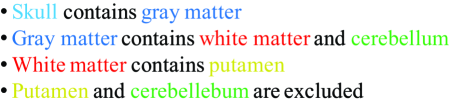

Abstract

Medical image segmentation, the task of partitioning an image into meaningful parts, is an important step toward automating medical image analysis and is at the crux of a variety of medical imaging applications, such as computer aided diagnosis, therapy planning and delivery, and computer aided interventions. However, the existence of noise, low contrast and objects’ complexity in medical images are critical obstacles that stand in the way of achieving an ideal segmentation system. Incorporating prior knowledge into image segmentation algorithms has proven useful for obtaining more accurate and plausible results. This paper surveys the different types of prior knowledge that have been utilized in different segmentation frameworks. We focus our survey on optimization-based methods that incorporate prior information into their frameworks. We review and compare these methods in terms of the types of prior employed, the domain of formulation (continuous vs. discrete), and the optimization techniques (global vs. local). We also created an interactive online database of existing works and categorized them based on the type of prior knowledge they use. Our website is interactive so that researchers can contribute to keep the database up to date. We conclude the survey by discussing different aspects of designing an energy functional for image segmentation, open problems, and future perspectives.

keywords:

Prior knowledge, targeted object segmentation, review, survey, medical image segmentation1 Introduction

Image segmentation is the process of partitioning an image into smaller meaningful regions based in part on some homogeneity characteristics. The goal of segmentation is to delineate (extract or contour) targeted objects for further analysis.

For example, in medical image analysis (MIA), image segmentation of organs or tissue types is a necessary first step for numerous applications, e.g. measuring tumour burden (or volume) from positron emission tomography (PET) or computed tomography (CT) scans (Hatt et al., 2009; Bagci et al., 2013), analyzing vasculature from magnetic resonance angiography (MRA) (e.g. measuring tortuosity) (Bullitt et al., 2003; Yan and Kassim, 2006), grading cancer from histopathology images (Tabesh et al., 2007), performing fetal measurements from prenatal ultrasound (Carneiro et al., 2008), performing augmented reality in robotic image guided surgery (Su et al., 2009; Pratt et al., 2012), building statistical atlas for population studies and voxel-based morphometry (Ashburner and Friston, 2000).

Given an input image, , the goal of a typical image segmentation system is to assign every pixel in a specific label where each label represents a structure of interest. Several traditional segmentation algorithms have been proposed for assigning labels to pixels; these include thresholding (Otsu, 1975; Sahoo et al., 1988), region-growing (Adams and Bischof, 1994; Pohle and Toennies, 2001; Pan and Lu, 2007), watershed (Vincent and Soille, 1991; Grau et al., 2004; Hamarneh and Li, 2009) and optimization-based methods (Grady, 2012; McIntosh and Hamarneh, 2013a; Ulén et al., 2013). The existence of noise, low contrast and objects complexity in medical images, typically cause the aforementioned methods to fail. In addition, all these traditional methods assume that objects’ entire appearance have some notion of homogeneity; however, this is not necessarily the case for complex objects (e.g. multi-region cells with membrane, nucleus and nucleolus; or brain regions affected by magnetic field of a magnetic resonance imaging (MRI) device non-uniformity). Many real-world objects are better described by a combination of regions with distinct appearance models. This is where more elaborate prior information about the targeted objects becomes helpful.

The majority of state-of-the-art image segmentation methods are formulated as optimization problems, i.e. energy minimization or maximum-a-posteriori estimation, mainly because of their: 1) formal and rigorous mathematical formulation, 2) availability of mathematical tools for optimization, 3) capability to incorporate multiple (competing) criteria as terms in the objective function, 4) ability to quantitatively measure the extent by which a method satisfies the different criteria/terms, and 5) ability to examine the relative performance of different solutions.

In this paper, we review the various types of prior information that are utilized in different optimization-based frameworks for segmentation of targeted objects. Prior information can take many forms: user interaction; appearance models; boundaries and edge polarity; shape models; topology specification; moments (e.g. area/volume and centroid constraints); geometrical interaction and distance prior between different regions/labels; and atlas or pre-known models. We compare the different methods utilizing prior information in image segmentation in terms of the type of prior information utilized, domain of formulation (continuous vs. discrete) and optimization techniques (global vs. local) used.

The rest of the paper is organized as follows. In Section 2, we briefly review the previous surveys that covered the medical image segmentation (MIS) problems and justify the need for our survey. In Section 3, we review the fundamentals of optimization-based image segmentation techniques. In Section 4, we give a concrete overview of the different types of prior knowledge devised to improve image segmentation. Finally, in Section 5, we summarize our notes and elaborate on future perspectives.